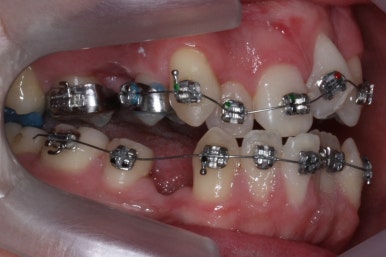

위아랫니가 각각 가지런해지고 있는 것을 볼 수 있습니다.

적절한 시기가 되면 악궁확장장치를 제거하고, 확장장치가 걸려있던 치아도 가지런하게 해줍니다.

윗니는 아직 가지런하게 하는 작업 중이며, 아랫니는 가지런하게 하는 작업은 거의 다 되었습니다.

이제 아랫니는 이 뽑은 자리를 앞뒤로 당겨서 없애주어야 합니다. 보통은 앞니가 뒤로 많이 들어오기 때문에 이번 환자분 처럼 앞니가 거꾸로 물리는 경우 앞니를 제대로 물리게 해줄 수 있습니다.

계속 윗니는 가지런히 해주고 있으며 아랫니는 앞뒤를 뒤로 당기고 있습니다.

거꾸로 물리던 앞니가 서서히 개선되어 가는 것을 볼 수 있습니다.

부산구순구개열 키다리아저씨치과에서 교정치료 하신지 1년여만에 드디어 앞니는 거꾸로 넘어왔고, 윗니들도 상당히 많이 가지런해졌습니다.

이 뽑은 자리도 상당히 많이 줄어든 것을 볼 수 있고, 이제는 정상적인 포개짐이 만들어졌습니다.